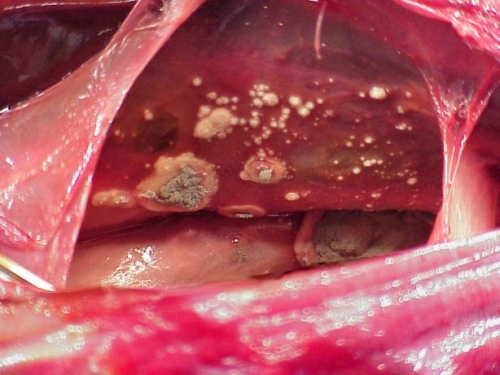

Aspergillosis en aves

Se trata de una enfermedad fungica que afecta el respiratorio de forma esporádica en muchas especies de aves, sobre todo las alojadas en lugares húmedos y poco ventilados. Se trata de una enfermedad oportunista no contagiosa causada por el hongo aspergillus que actua como alérgeno o como patógeno invasivo.

La enfermedad suele estar localizada en respiratorio superior (sobre todo en siringe) pero también puede afectar los sacos aéreos y los pulmones, aunque también puede dispersarse a otros órganos. Suele haber cuadros agudos y crónicos, difusos y localizados. Entre las psitácidas, el yaco de cola roja, los pionus y los amazonas son los que muestran una mayor sensibilidad.

En las radiografias podemos a veces, localizar las lesiones micoticas, sobre todo si son muy grandes. La endoscopia también nos permite a veces evidenciar granulomas y nódulos y podemos sacar muestras para citología.